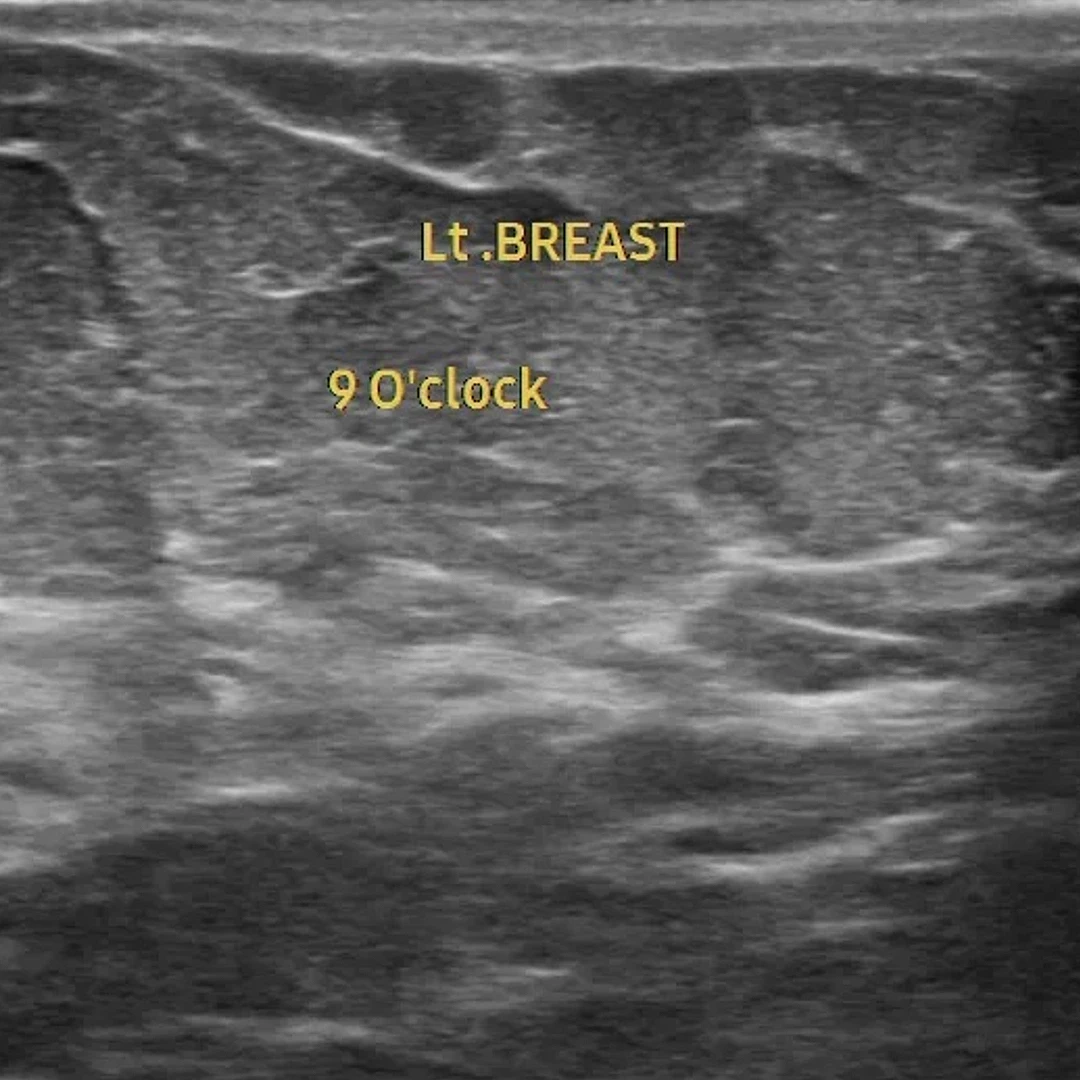

Breast Ultrasound

Breast Ultrasound uses sound waves to evaluate breast tissue, helping detect cysts, lumps, or other abnormalities. It’s often used alongside mammography for a more complete breast assessment.